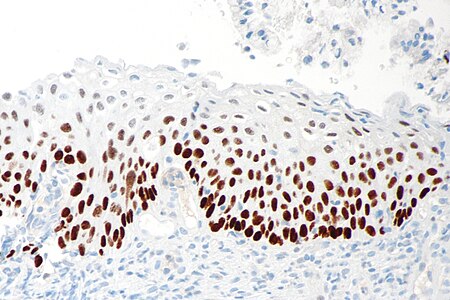

CIN3 must have full thickness atypia. When faced with not-so-straight-forward biopsies where the pathologist is debating between benign mimics of HSIL, such as immature metaplasia or atypical atrophy, utilizing the biomarker p16 may help distinguish them, as p16 shows intense and continuous staining in HSILs and suggests infection with a high-risk HPV type. [6][7]

Figure

High-grade squamous intraepithelial lesion of the cervix (HSIL). High nuclear-to-cytoplasmic ratio, nuclear abnormalities of high grade dysplasia. Compare with the normal squamous cell nuclear size of the surrounding cells.

Pap stain, 40x. Contributed (more…)